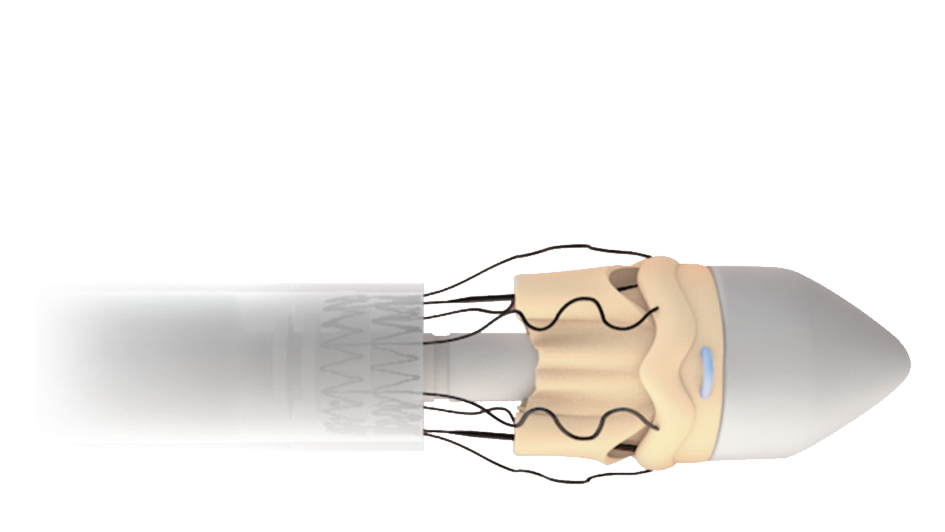

Designed for MICS

Perceval Plus RelyON System and Minimally Invasive Cardiac Surgery were made for each other thanks to the sutureless design of the valve and the length and diameter of the new Deliver System. The System allows for minimized incision,11,15 maximized visibility11,12, faster learning curve14,15 and a reduced manipulation of the aortic root.11,15,16

Minimized incision11,12

Thanks to the unique collapsible profile and sutureless design of the valve and the design of the Delivery System, Perceval Plus RelyON System allows a reduced incision size and less surgical trauma.2,11,17

Maximized visibility during implantation11,12

The collapsible profile of the valve and the small diameter of the Delivery System allow the surgeon full visibility of the annulus and of the anatomical structures during implantation and deployment for great confidence and fast, precise positioning at the implantation site.2,8

Precise

The RelyON Delivery System delivers Perceval Plus with a single movement of the hand allowing to maintain a firm hold on the device, which in turn facilitates a precise positioning of the valve in the aortic root.

Optimized for MICS procedures

The design of the Delivery System is optimized for MICS. Both the length and the small diameter of the shaft, together with the collapsible design of Perceval Plus, allow for a minimized incision and facilitated access to and visualization of the implantation site.